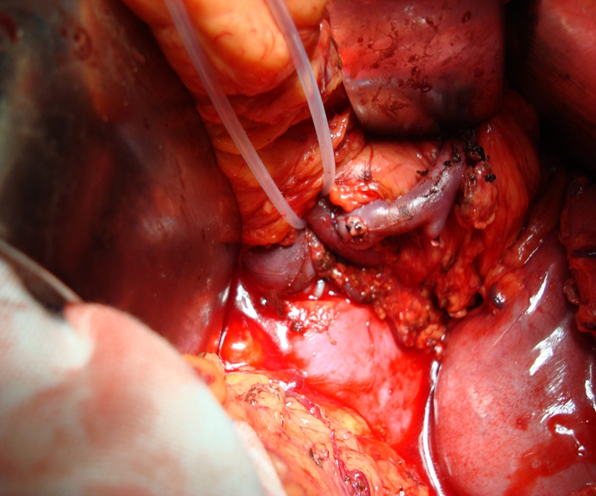

急诊 TIPS 应用

对于内镜反复止血失败的急性上消化道大出血患者,TIPS 可作为救命手段。我们曾接诊术中持续呕血的危重患者,通过急诊 TIPS 成功止血。

急性上消化道大出血急诊TIPS